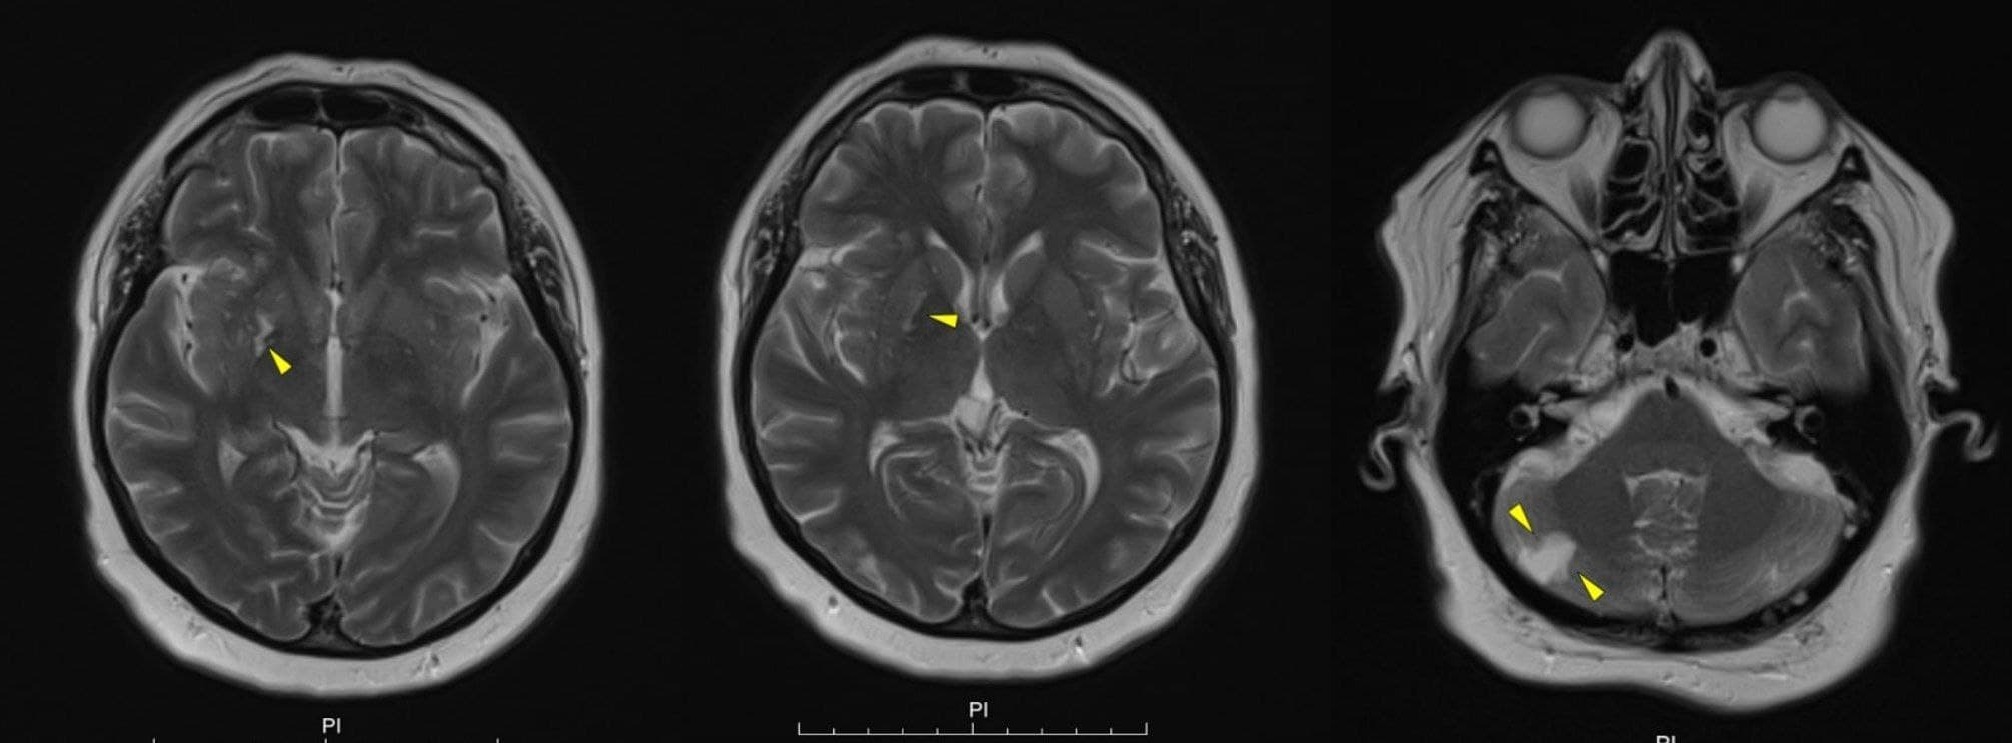

МРТ головного мозга (выполнено после получения лечения)

Кисто-глиозные изменения в области правой скорлупы и правом полушарии мозжечка. Надо отдельно сказать, что МРТ стало доступно к выполнению только на фоне лечения.

В случае с нашей пациенткой очаг расположился в скорлупе что, тем не менее, не противоречит общей идее о патогенезе ее двигательного нарушения.